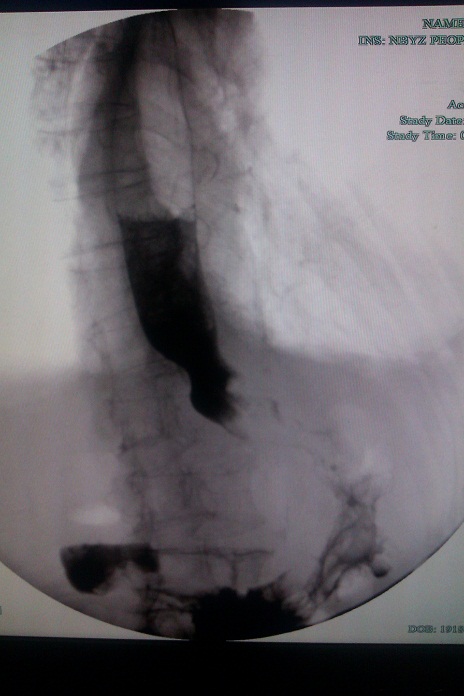

近期,我科就成功为一名94岁高龄男性近端胃癌患者成功放置了金属支架。该患者发现胃癌1年,近几个月开始出现进食后呕吐,但患者食欲很好,精神状态尚可,我们对该患者进行了评估,其有放置金属支架的指征,遂安排金属支架置入术。手术顺利,术后患者无明显腹痛等不适,进食后未再出现呕吐情况。虽然对于疾病本身,我们已无能为力,但该姑息治疗能解决患者不能进食的痛苦,一定程度上,延长了患者的生存时间。